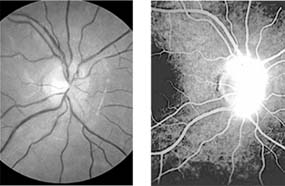

Figure 14-9

Figure 14-9: Mild papilledema. The disk margins are blurred superiorly and inferiorly by the thickened layer of nerve fibers entering the disk.